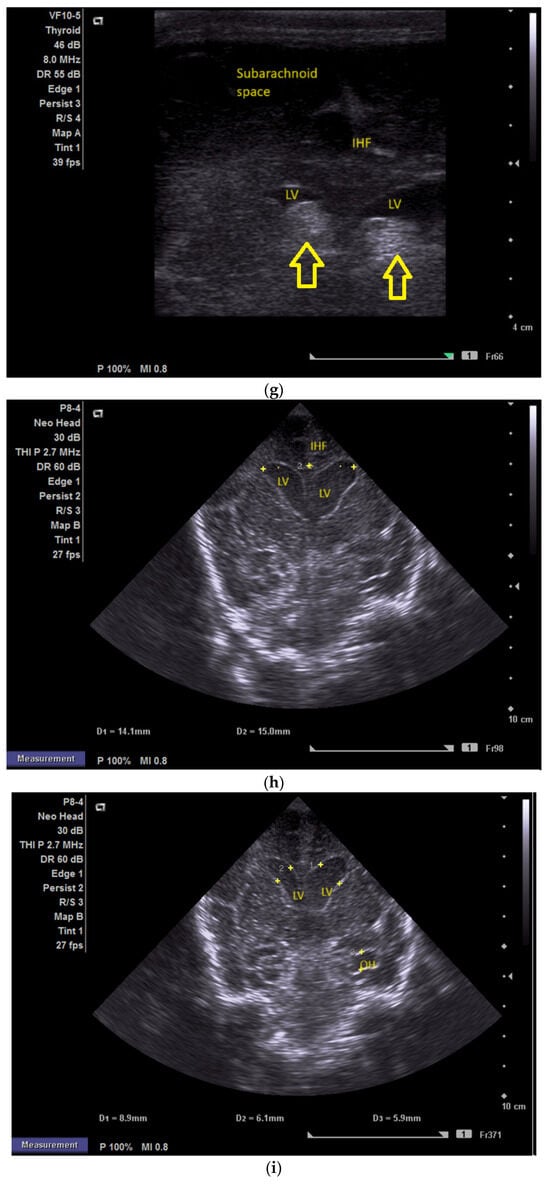

The first CUS was performed 24 h after birth and showed dilation of the third and fourth lateral ventricles, enlargement of the Sylvius aqueduct, and the presence of an arachnoid cyst (Figure 3a–e).

(a) Cranial ultrasound. Coronal view. Enlargement of the lateral ventricles with hyperechoic and third ventricle dilation. D1, D2—Levine index measurement. D3, D4—anterior horn width measurement. D5—third ventricle (personal image collection). (b) Cranial ultrasound. Sagittal view. Up—left ventricle. D1, D2—lateral ventricle measurements and thalamo-occipital horn width. Down—right ventricle. D1, D2—lateral ventricle measurements and thalamo-occipital horn width (personal image collection). (c) Cranial ultrasound. Sagittal view. Up—enlargement of the third and fourth ventricles. Measurements of the ventricles. Down—measurement of the resistive index (RI) performed on the anterior cerebral artery (ACA) using Doppler flow measurements. RI—0.74 (personal image collection). (d) Cranial ultrasound. Transtemporal view. Yellow arrow—enlargement of the Sylvian aqueduct (personal image collection). (e) Cranial ultrasound. Sagittal view. Yellow arrow—arachnoid cyst posterior to the third ventricle (personal image collection). (f) Cranial ultrasound. Coronal view. Lateral ventricles and third ventricle enlargement. D1, D2—Levine index measurement. D3, D6—right lateral ventricle measurement (anterior horn width). D4, D5—left lateral ventricle measurement (anterior horn width) (personal image collection). (g) Cranial ultrasound. Sagittal view. Left—left ventricle. D1—thalamo-occipital distance measurement. Right—right ventricle. D2—thalamo-occipital distance measurement (personal image collection). (h) Cranial ultrasound. Coronal view. Up—orange arrow—third ventricle. Red arrow—fourth ventricles. Yellow arrow—arachnoid cyst. Down—resistive index measured on the anterior cerebral artery. RI—0.79 (personal image collection). (i) Cranial ultrasound. Transversal view. Up—RI precompression value on the middle cerebral artery performed with Doppler examination. RI—68. Down—RI post-compression value on the middle cerebral artery performed with Doppler examination. RI—0.79 (personal image collection). (j) Cranial ultrasound. Up—coronal view. L1, L2—Levine index measurement of the lateral ventricles. Down—sagittal view. L1, L2—measurement of the thalamo-occipital distance (personal image collection). (k) Cranial ultrasound. Sagittal view. L1, L2—measurement of the third ventricle. L3, L4—measurement of the fourth ventricle. L5, L6—measurement of the arachnoid cyst (personal image collection). (l). Head circumference-for-age. “X” symbols represent the measurements performed from birth and follow-up examinations. Head circumference was still under the curve during follow-up examinations (personal image collection) [28].

The CUS examination performed at 48 h after birth showed increases in the diameters of all ventricles. The resistive index presented an increase as well. The bregmatic fontanelle started bulging. The dimensions of the Sylvian aqueduct were not modified (Figure 3f–h).

The CUS examinations performed at four days and seven days after birth showed stabilization regarding the values of the diameters. The pre- and post-compression values of the resistive index of the middle cerebral artery showed a delta-RI of 0.11 (pre—0.68, post—0.79, Figure 3i).

After discharge, at three weeks after birth (follow-up examination), the ventricle measurements showed wider ventricles and the arachnoid cyst was still present (Figure 3j,k).

The next follow-up examination performed a week later showed a delta-RI of 0.12 and an increase in the cranial perimeter (+ one cm since the last follow-up).

At 12 weeks of life (five week corrected age), ventricle dilations were still present. Neurological examinations showed axial and limb hypotonia. The general movement examination showed a poor repertoire with a General Movement Optimality Score (GMOS) of 19. At 18 weeks of life (11 week corrected age), the neurological exam revealed that the infant presented plagiocephaly and could keep eye contact, and during the traction-to-sit maneuver showed hypotonia of the neck muscles. In the prone position, the infant was unable to hold the head up. The passive tone assessment showed the “scarf sign”, with the elbow at the midline bilaterally and a popliteal angle of 90° on the right and 110° on the left. Deep tendon reflexes were present. The general movement (GM) assessment revealed absent fidgety movements, with a Motor Optimality Score (MOS) of 13.